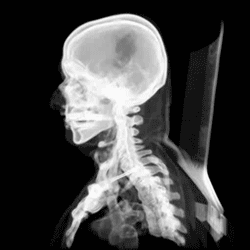

Че́реп (лат. cranium) — костная или хрящевая часть головы[1][2] у позвоночных животных, каркас головы, защищающий от повреждения наиболее уязвимые органы и служащий местом прикрепления её мягких тканей. Он поддерживает структуры лица и создает защитную полость для головного мозга и хорошо защищённые глазницы для глаз[3].

Череп состоит из двух отделов: висцерального (лицевого) и мозгового (черепная коробка). Причём у человека, в отличие от животных, мозговой череп значительно преобладает над лицевым. Все кости черепа, кроме нижней челюсти и подъязычной кости[6], соединены неподвижным соединением[7].

Считается, что человеческий череп состоит из двадцати двух костей — шести костей мозгового черепа и девяти костей лицевого скелета. В нейрокраниуме это затылочная кость (лат. os occipitale), две височные кости (лат. os temporale), две теменные кости (лат. os parietale), клиновидная (лат. os sphenoidale), решётчатая (лат. os ethmoidale) и лобная кости (лат. os frontale)

Костями лицевого черепа являются сошник (лат. os vomer), две нижних носовой раковины (лат. concha nasalis inferior), две носовых кости, две челюсти: пара верхнечелюстных костей (лат. maxilla), одна нижняя челюсть (лат. mandibula), две небные кости (лат. os palatinum), две скуловых кости (лат. os zygomaticum), и две кости слёзных (лат. os lacrimale). Некоторые источники включают подъязычную кость (лат. os hyoideum)[6] или три косточки среднего уха, но в целом общее мнение о количестве костей в человеческом черепе двадцать три, включая подъязычную.

Существуют каналы и отверстия в черепе. Самым большим из них является большое затылочное отверстие, через которое проходит продолговатый и спинной мозг, а также черепные нервы и кровеносные сосуды.

Череп человека

Разница между черепом человека и человекообразных обезьян заключается прежде всего в том, что человеческий череп по своей форме приспособлен к прямохождению. Голова балансирует на позвоночнике, из-за чего шейная мускулатура менее развита, а сам череп тоньше. Передняя часть черепа у человека более плоская, а объём краниальной полости значительно больше, для того, чтобы в него вмещался расширившийся в объёме мозг.